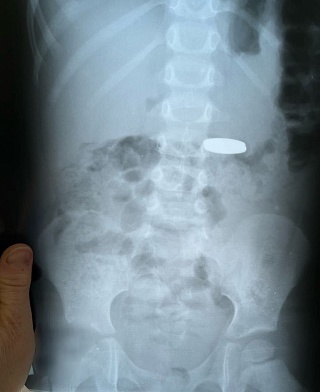

Девочка проглотила монету во время игры.

В стационар Балаковской городской клинической больницы поступила девочка девяти лет. Она рассказала, что играла с друзьями во дворе. При себе у нее была пятирублевая монета. Об этом сообщается в телеграм-канале медучреждения.

Под общим наркозом монетка была извлечена из пищевода ребёнка.

По слова медиков, обращение к врачам было своевременным, так монета застряла на входе в пищевод. В таких случаях медлить нельзя, последствия могут быть необратимы.

В минувшие выходные аналогичная помощь была оказана другому пациенту - трехлетнему мальчику, малыш проглотил две монетки по два рубля.